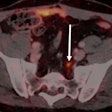

Ga-68 PMSA PET/CT tops for prostate cancer recurrence

Ga-68 PSMA-11 PET/MRI improves prostate cancer detection